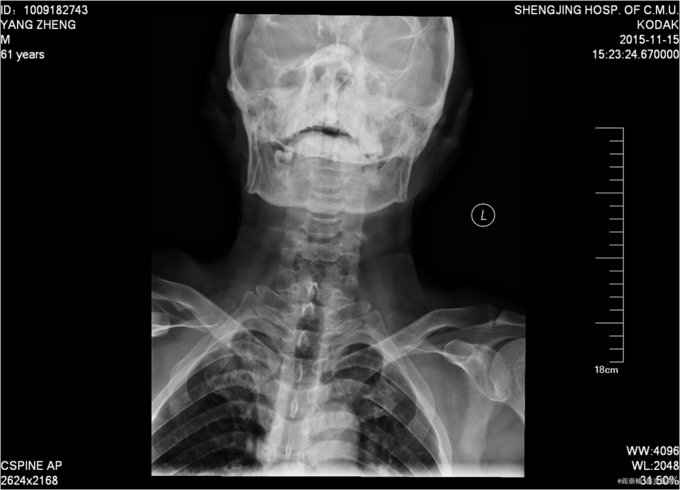

患者于2015年11月13日15:30左右因在工厂2米高管道上作业不慎坠落致颈部疼痛,四肢活动受限,受伤后被家人送入当地北台镇医院,输一袋葡萄糖液,转入本溪二院,行口腔科、眼科缝合行X线检查,头颅ct检查。患者及家属为求系统治疗,急来我院,急诊予以行辅助检查,提示:颈4-6棘突骨折,颅骨多发骨折;急诊以“颈椎外伤”为主诊断收入我科。病来患者一般状态无头晕及头痛,,无恶心及呕吐 ,留置导尿中。

前额部敷料包扎中,打开敷料见右眉处7cm大小创口已缝合,无渗出,前额处可见一5cm大小创口已缝合,颈领保护中,触痛。双手感觉减退。患者平乳头以下触觉存在,痛觉及运动消失。屈肘肌力(R4,L4),伸肘肌力(R0,L0),手掌掌屈肌力(R0,L0),手掌背伸肌力(R0,L0)。双手握力(R0,L0)。髂腰肌肌力(L0级,R0级),伸膝力(L0级,R0级),足背伸力(L0级,R0级),足跖屈肌力(L0级,R0级),神经反射:BCR:L(-)R(-),TCR:L(-)R(-),肱桡肌反射:(-)R(-),PSR: L(-)R(-),ASR: L(-)R(-),Hoffmann Sign:L(-)R(-), Babinski Sign L(-)R(-) 双侧桡动脉、足背动脉可扪及搏动,末梢血运良好。